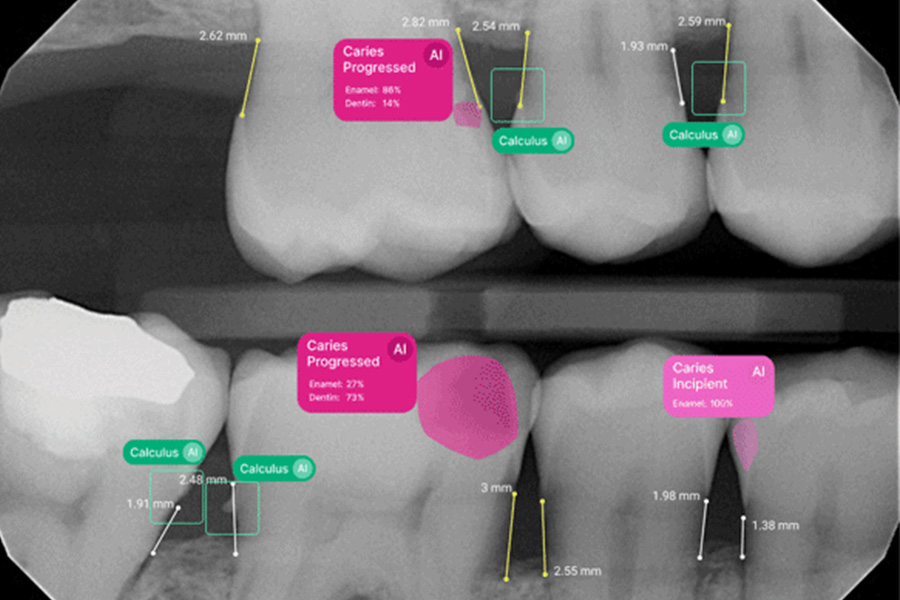

Imagine catching a cavity before it causes pain or spotting signs of gum disease while it’s still easy to treat. That’s exactly what’s possible at Tomase Dental Care. Dr. Timothy Tomase now uses Pearl AI’s dental software. This advanced AI tool analyzes your X-rays in real time and immediately highlights potential concerns. With this added insight, we can take a more proactive approach to keeping your smile healthy.

Pearl AI works like an extra set of expert eyes. While we take your X-rays, the software instantly scans each image and highlights anything that needs a closer look. It also pulls in your dental records so Dr. Tomase can see the full picture and build a care plan that fits your needs.

Pearl AI helps us detect issues earlier, diagnose more accurately, and give you a clearer understanding of your dental health. Here’s how this technology supports your care: